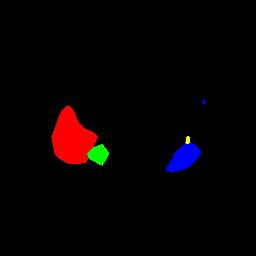

To better retain the deep features of an image and solve the sparsity problem of the end-to-end segmentation model, we propose a new deep convolutional network model for medical image pixel segmentation, called MC-Net. The core of this network model consists of four parts, namely, an encoder network, a multiple max-pooling integration module, a cross multiscale deconvolution decoder network and a pixel-level classification layer. In the network structure of the encoder, we use multiscale convolution instead of the traditional single-channel convolution. The multiple max-pooling integration module first integrates the output features of each submodule of the encoder network and reduces the number of parameters by convolution using a kernel size of 1. At the same time, each max-pooling layer (the pooling size of each layer is different) is spliced after each convolution to achieve the translation invariance of the feature maps of each submodule. We use the output feature maps from the multiple max-pooling integration module as the input of the decoder network; the multiscale convolution of each submodule in the decoder network is cross-fused with the feature maps generated by the corresponding multiscale convolution in the encoder network. Using the above feature map processing methods solves the sparsity problem after the max-pooling layer-generating matrix and enhances the robustness of the classification. We compare our proposed model with the well-known Fully Convolutional Networks for Semantic Segmentation (FCNs), DecovNet, PSPNet, U-net, SgeNet and other state-of-the-art segmentation networks such as HyperDenseNet, MS-Dual, Espnetv2, Denseaspp using one binary Kaggle 2018 data science bowl dataset and two multiclass dataset and obtain encouraging experimental results.